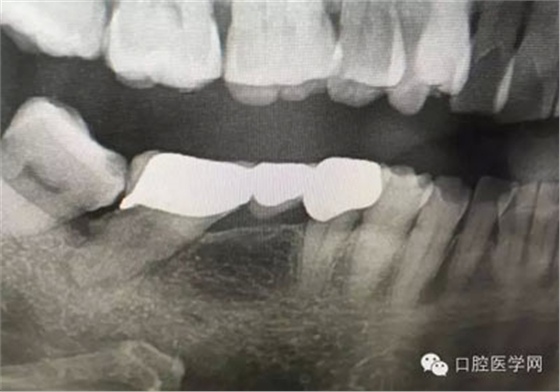

根管再治療是我們比較頭疼的,尤其是那些冠修復(fù)過(guò)的,我們有很多的麻煩需要去溝通,比如可能導(dǎo)致的側(cè)穿、可能沒有看到的腐質(zhì)、可能導(dǎo)致的崩瓷,或者是后期可能出現(xiàn)冠折......這些需要我們和患者好好的溝通。全瓷冠還好些,金屬冠根測(cè)的時(shí)候很是麻煩,總之我們做修復(fù)的時(shí)候不要單純的追求速度,追求效益,適當(dāng)?shù)淖⒁庀挛覀兊幕A(chǔ)治療和設(shè)計(jì)。

這是一例外院樹脂修復(fù)后十個(gè)月出現(xiàn)牙髓炎癥狀的患者。遇到這樣子的患者大家會(huì)怎么做,證明選擇,還有就是可做可不做治療的如何去平衡。